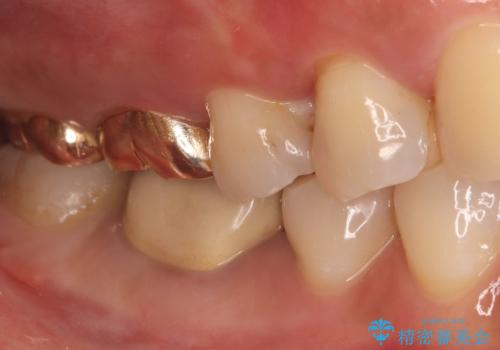

- 主訴:一番奥の歯の奥側の面に虫歯があるのを治したい

クリーニングにいらした患者さんで、右下7番目の歯の奥側の面や手前の歯との間にう蝕があり、噛む面にも蝕処置によるレジン材料が詰まっていたことから、う蝕も古い材料も全て除去しセラミックインレーでのやり替えとなりました。

右下7近遠心にカリエスを認め、咬合面のCR修復も劣化していたので、カリエスと古い材料を全て除去し新しくCR裏層した後、セラミックインレーをセットしています。セット時はラバーダム防湿を行っています。